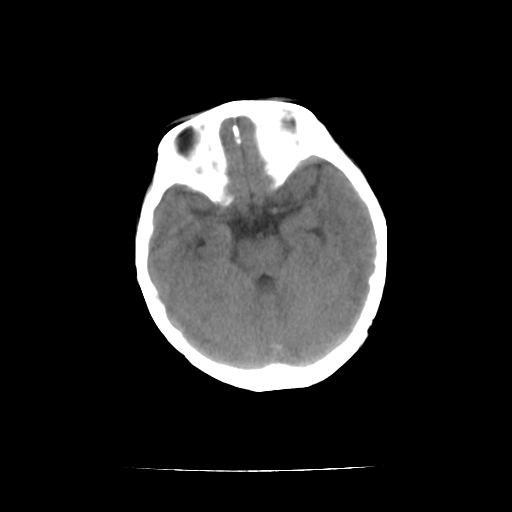

女,10个月,头外伤三天,伤后爱哭闹,吃奶少,睡觉不踏实。

左侧颞极蛛网膜囊肿

1)左侧颞极蛛网膜囊肿。2)第四脑室出血?

1、左侧颞极蛛网膜囊肿;2、第四脑室出血?3、右侧顶叶脑裂畸形伴灰质异位?

1)左侧颞极蛛网膜囊肿。2)第四脑室内高密度影,性质待定。